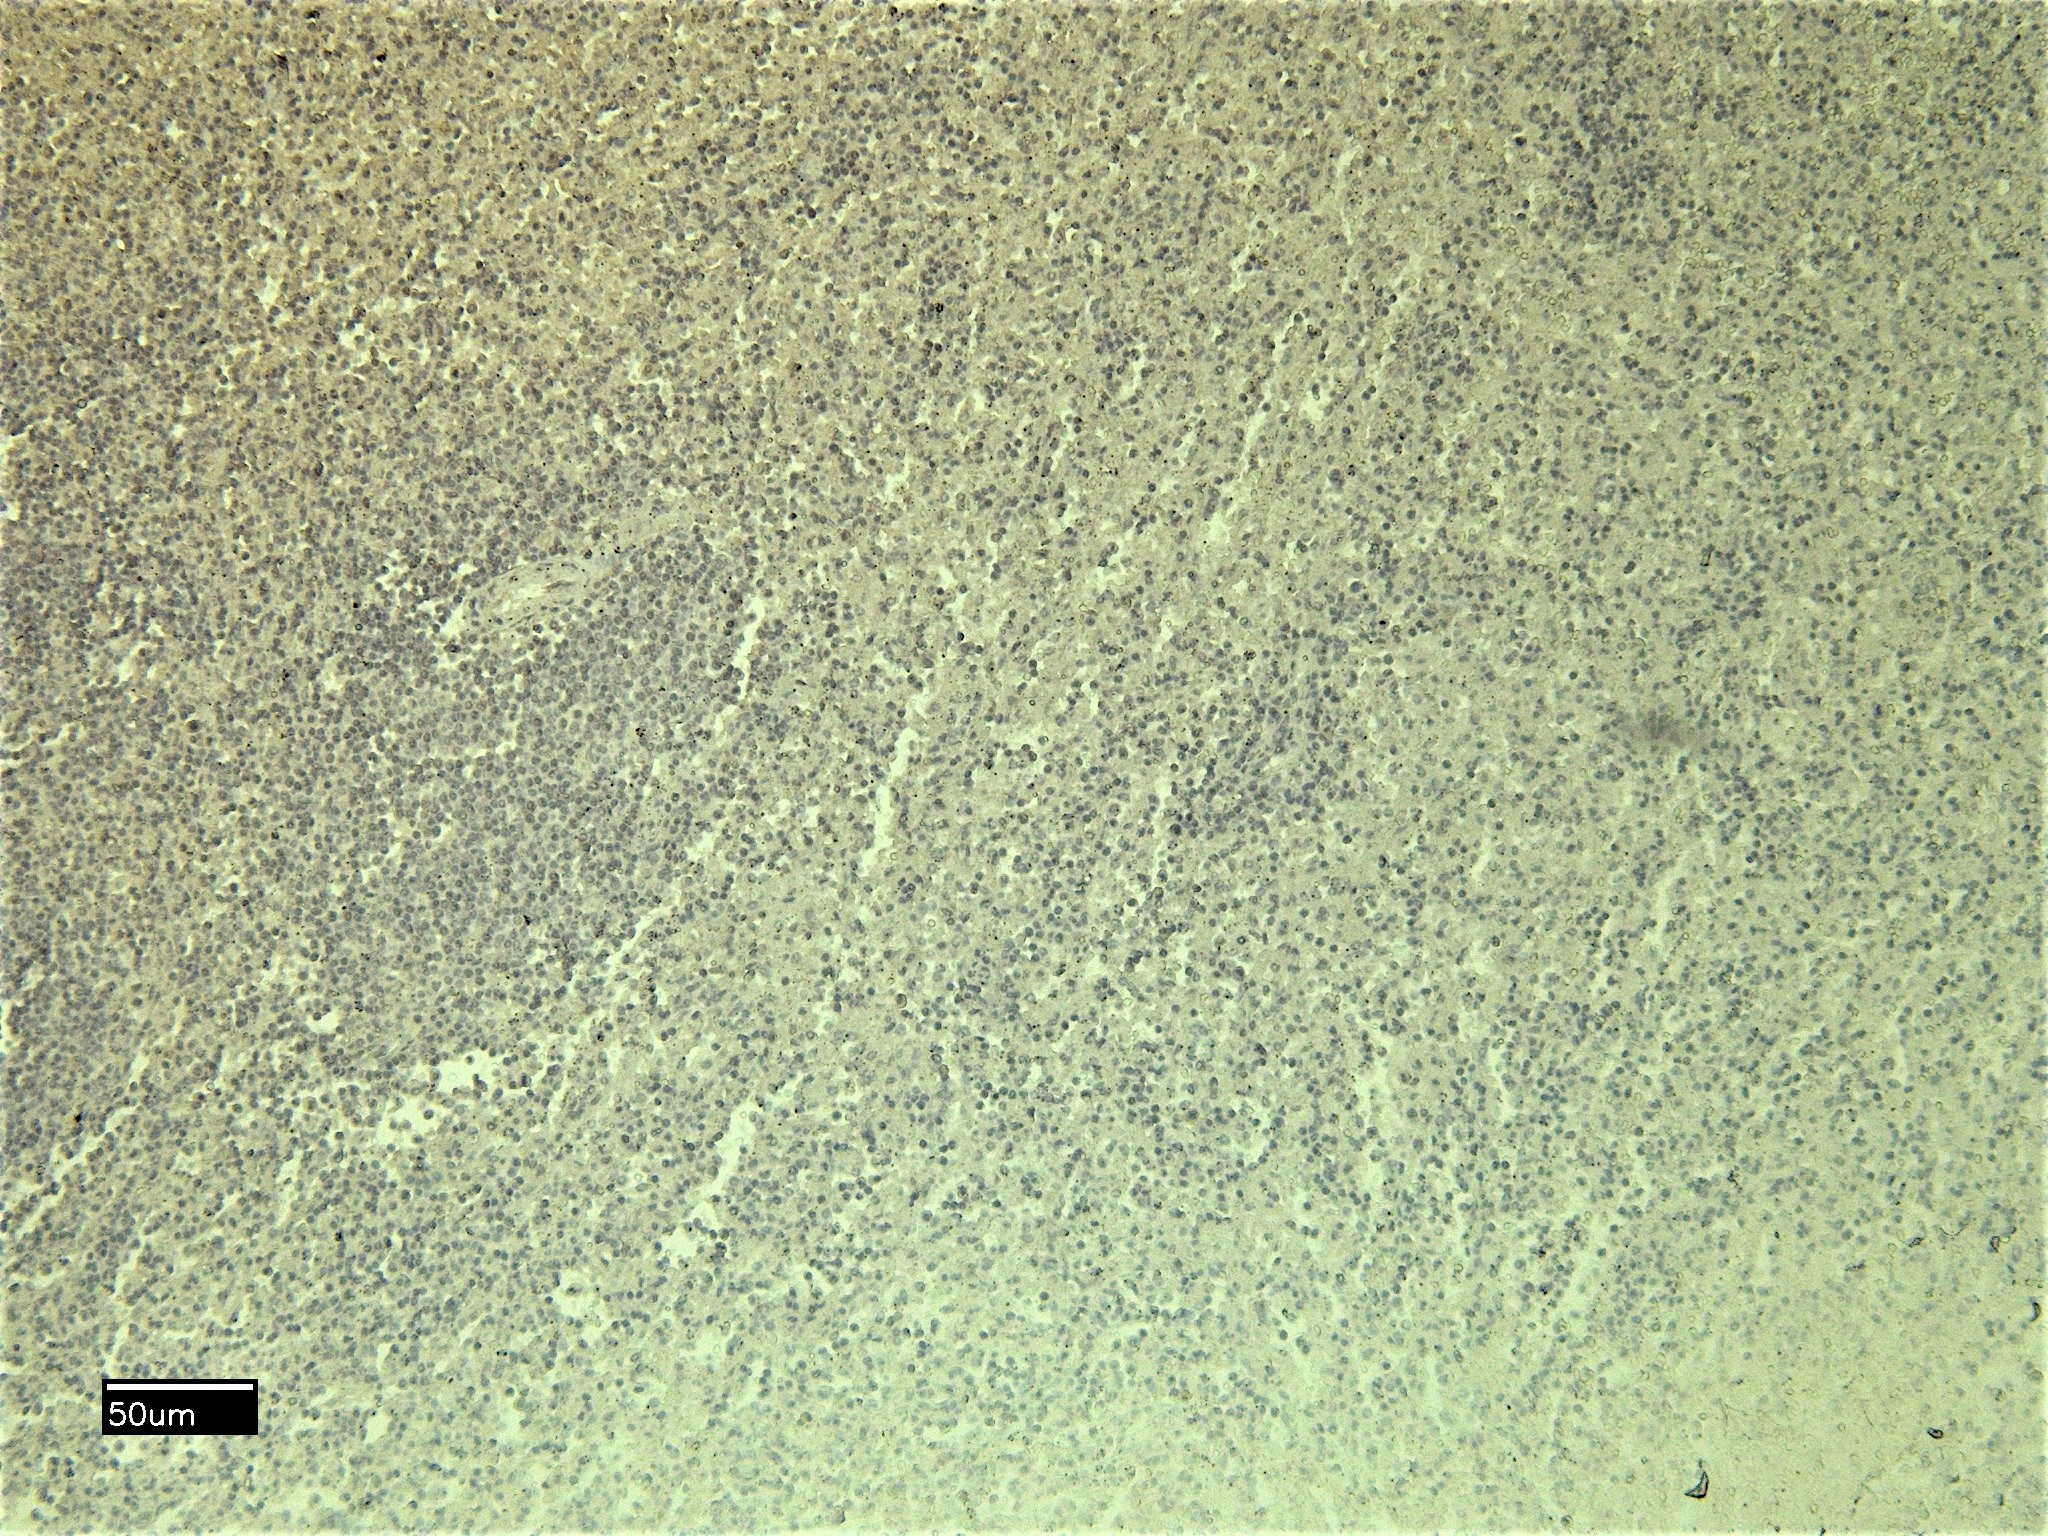

IHC Results Paraffin embedded Human Spleen. Recommended concentration: 6-8µg/ml. | |